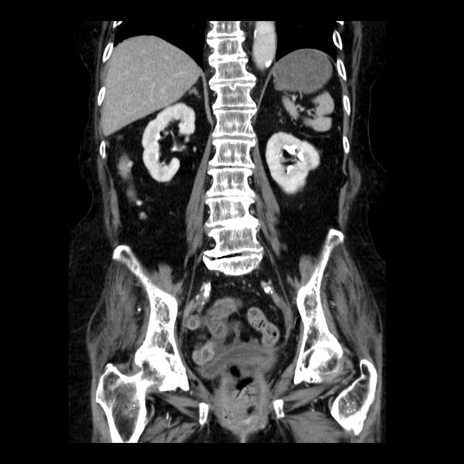

症例14(冠状断像)

【症例】 90歳代女性

【主訴】 腹痛・嘔吐

【現病歴】今朝から左側腹部痛を認めた。 経過観察していたが、嘔吐を認めたため来院。

【既往歴】 子宮癌術後

【身体所見】 意識清明、BP 127/54mmHg、P 98bpm Sp02 95%(RA)、BT 35.8°C、腹部平坦・軟腸ぜん動音聴取良好、右下腹部圧痛(+) 反跳痛なし

【データ】WBC 9800、CRP 0.46